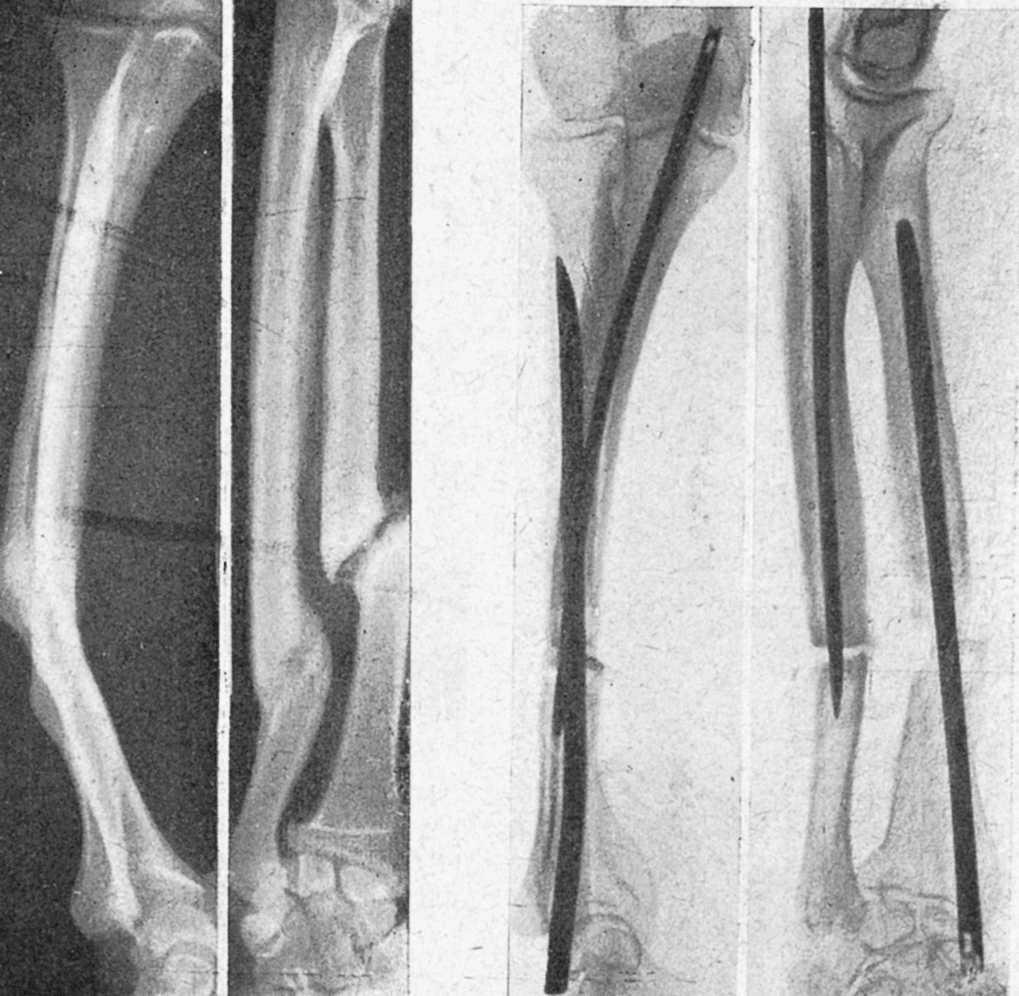

Figura 11. Complicación que se produce por no seleccionar bien el diámetro del clavo; astillamiento del fragmento proximal.

Figura 12. Otra complicación de enclavijamiento cerrado; el fragmento proximal estallado ha sido penetrado por el distal en cuña al impactar; el control radiográfico puso en evidencia el accidente y hubo que retirar el tallo y reducir la penetración; curó sin complicaciones.

Figura 13. Fractura tercio medio fémur con gran desviación fragmentaria, irreducible por interposición muscular, tributaria de la reducción cruenta. La misma, enclavijada y en período de consolidación; callo perióstico exuberante.

Teniendo presente todo lo expuesto, y muy presente las ventajas de contención que presenta el procedimiento, comenzamos a usar, antes de disponer de tallos, alambres de Kirschner intramedulares en las fracturas de antebrazo, procedimiento con el que hemos obtenido buenos resultados y que continuamos utilizando, colocando alambres en ambos huesos o alambre en radio y tallo de Küntsche en el cúbito, sobre todo en fracturas bajas de este hueso, para evitar el «décalage», que el alambre no evita. Esta técnica con alambres la hemos extendido a casos atípicos en los que, introducido oblicuamente, su elasticidad le hace obrar de ballesta y permite mantener reducciones difíciles por otros procedimentos.